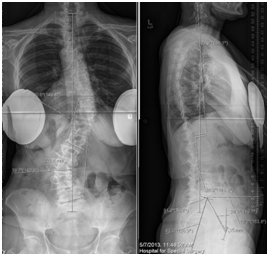

- Reduced normal dorsal kyphosis (Figure 1).

Figure 1 Compensation (Lumbar Kyphosis )à Decrease in S S ↑ Increase in PT, Hip Extension, Knee bend , Decrease in thoracic curve.